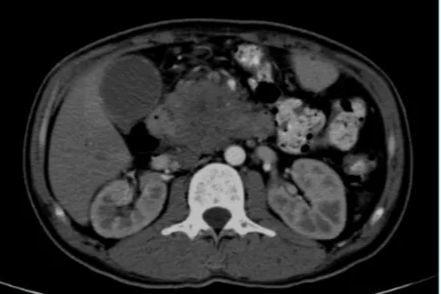

37 岁青年胰腺癌绝境重生,纳米刀技术点燃生命希望